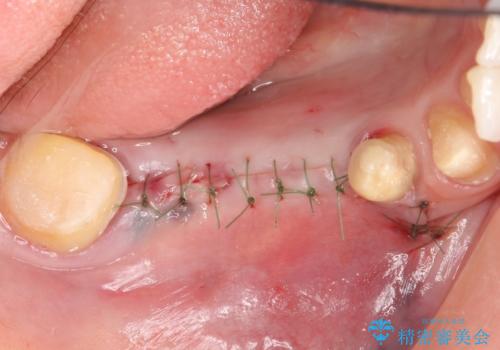

右下6番目の歯を診査したところ歯根が破折していたため、保存不可能であることを説明し抜歯しました。

その後右下5、6番目にはインプラントを埋入し、右下3、4、5、6、7番の歯の補綴をオールセラミッククラウンによって行いました。

- 外科手術のため、術後に痛みや腫れ、違和感を伴います